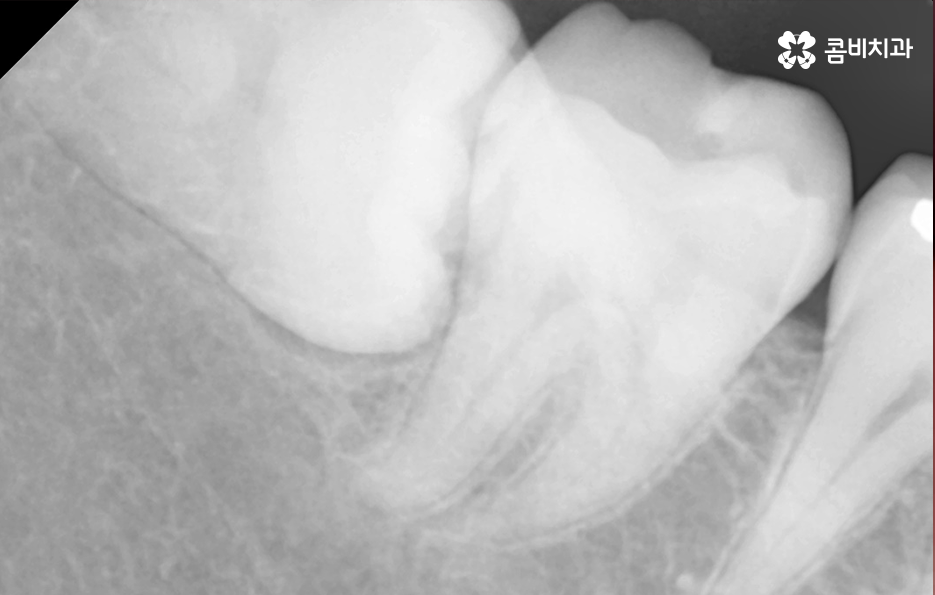

저작 기능에서 주된 역할도 하지만 위 사진을 다시 보시면 사랑니가 부분 매복되어 있는 상태로 누워서 자라고 있기 때문에 사랑니와 어금니 인접면에서 청결 관리가 잘 안되는 문제로 충치나 치주질환을 앓고 계신 분들도 많기 때문에 사랑니로 인해 어금니 문제가 발생하는 경우도 많이 있어요

다시 위 어금니 사진을 살펴보면 사랑니가 매복되어 있긴 하지만 위쪽 부분이 살짝 잇몸 밖으로 드러나 있는 것을 볼 수 있는데요. 평소 칫솔질을 잘하더라도 사랑니로 인해 청결관리에 미흡한 점이 생기면 주변 치아에도 충치가 전염되는 등의 안좋은 영향을 주는 경우가 많으며 부분 매복 사랑니의 경우 충치가 아니더라도 잇몸 염증의 주된 원인이 되고 있기 때문에 발치하는 것을 각종 구강질환을 예방하기 위해 권하고 있어요

오늘 케이스 사진의 경우 사실상 사랑니 하나만 보더라도 주변 치아에 충치 및 치주질환을 일으키기 쉬운 사례이며 누운 사랑니로 인해서 어금니의 씹는면 만이 아니라 인접면 충치나 손상으로 이어지기 사례로도 볼 수 있는데요